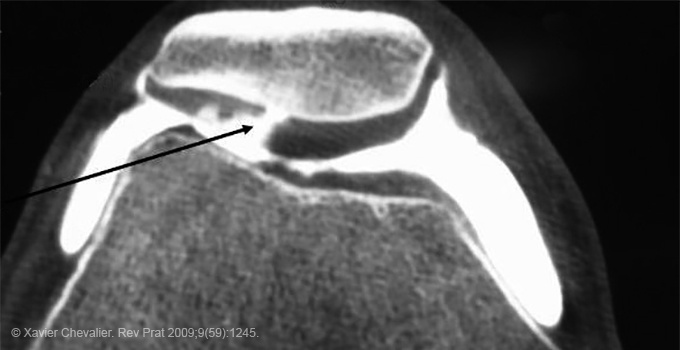

L’arthrose peut atteindre toutes les articulations ou seulement une partie, avec une prédominance au niveau des membres inférieurs (genoux, hanches), du rachis, des mains… Les radiographies standard peuvent être normales ou retrouver des lésions arthrosiques. Les imageries de type IRM sont réalisées en cas de doute diagnostique ou dans le cadre de la discussion d’une prise en charge chirurgicale.